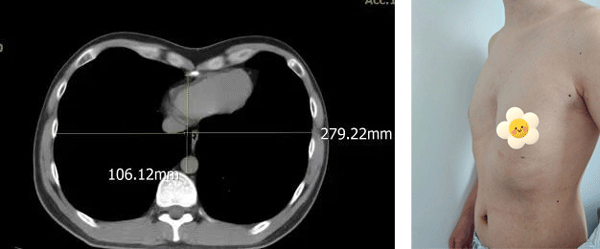

查体可见前胸壁凹陷,两侧胸壁向内收缩塌陷,左右胸廓对称,最深处位于“心口窝”上方,脊柱对称无侧弯。入院后科室经过详细术前讨论,考虑患者漏斗胸加重,出现胸闷、心悸等不适,并且畸形影响美观,对患者造成心理不适,同时患者本人手术意愿强烈,因此我们于2025年8月14日在全麻下给患者实施了微创胸腔镜漏斗胸矫正术(NUSS手术),手术历时2小时,过程顺利。于胸腔镜引导下精准置入矫形钢板,胸骨抬举满意,胸廓外形即刻得到改善。

术前CT及胸部图